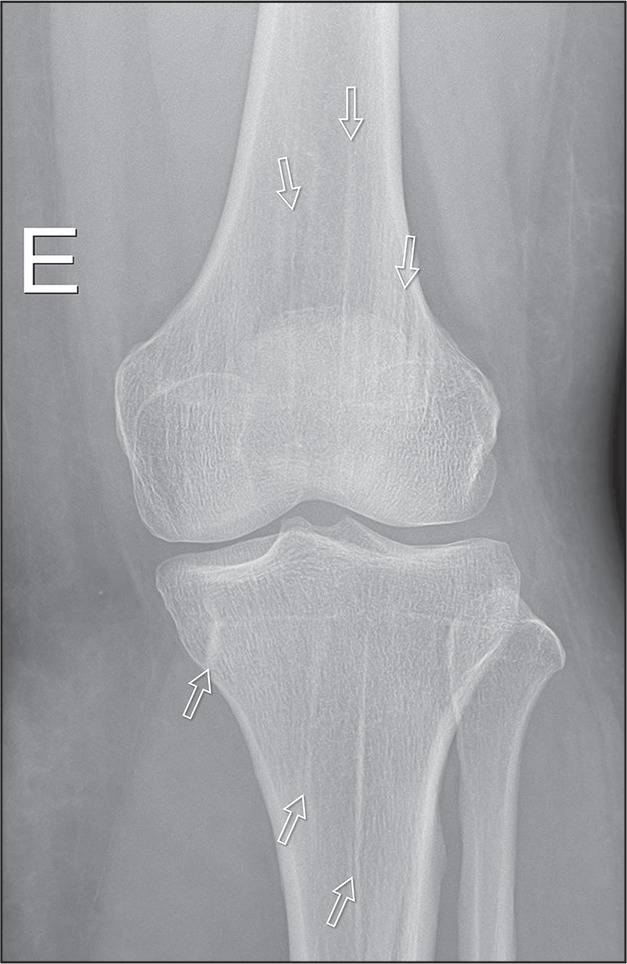

硬化性骨发育不良包括骨密度异常,分为遗传性和非遗传性形式。主要通过x线摄影诊断,通常是偶然发现的。在遗传形式中,以下是最突出的:骨质疏松症、骨质疏松症、多发性骨干硬化(肋病)、纹状骨病和Camurati-Engelmann病。在非遗传性形式中,髓内骨硬化和骨质疏松症具有特定的影像学特征。主要的鉴别诊断包括成骨细胞转移、结节性硬化症和肾性骨营养不良,由于它们的相似性,需要仔细鉴别。

Sclerosing bone dysplasias encompass abnormalities in bone density, divided into hereditary and nonhereditary forms. Primarily diagnosed through radiography, they are often incidental findings. Among the hereditary forms, the following stand out: osteopetrosis, osteopoikilosis, multiple diaphyseal sclerosis (ribbing disease), osteopathia striata, and Camurati-Engelmann disease. Among the nonhereditary forms, intramedullary osteosclerosis and melorheostosis present specific radiographic characteristics. The main differential diagnoses include osteoblastic metastases, tuberous sclerosis, and renal osteodystrophy, requiring careful differentiation because of their similarities.